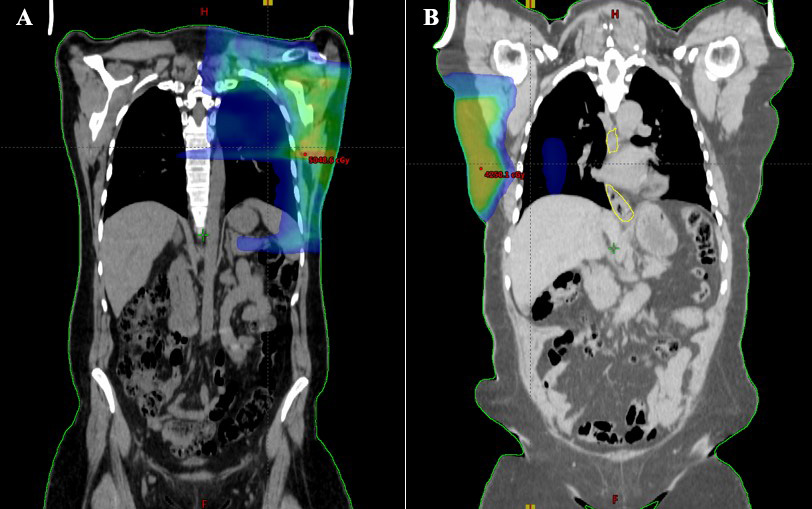

According to the 3D planning evaluation of the patients, the Varian Eclipse Vers 15.6 planning algorithm could not detect measurable doses in both the ipsilateral and contralateral ovaries. According to our results, the ovarian doses in adjuvant radiotherapy of breast cancer patients who received RT with the 3D technique were zero (Fig. 1A). In the helical IMRT planning system, ovarian doses were very low and these doses were expressed as cGy, which is one-hundredth of a Gy (Fig. 1B). In helical IMRT plans, the ipsilateral ovary dose was median 12 (range 10–30) cGy; the contralateral ovary dose was median 8 (range 5–13) cGy (Table 1). In patients with MRM, ipsilateral ovary dose in helical IMRT plans was median 10 (range 10–13); in patients with BCS, it was median 15 (12–30) cGy. In patients with MRM, contralateral ovary doses in helical IMRT plans was median 6 (range 5–8) cGy; in patients with BCS, it was median 8 (range 7–13) cGy (Table 2, Fig. 2).

Fig. 1.Computerized tomography (CT) field size image of patients simulating radiotherapy. The ovarian doses in adjuvant radiotherapy of breast cancer patients who received radiotherapy (RT) with the three-dimensional (3D) technique were zero (A). In the helical intensity modulated radiotherapy (IMRT) planning system, ovarian doses were very low (B).